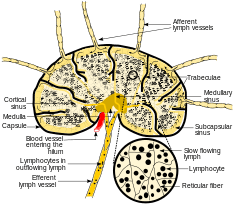

Diagram of a lymph node, showing the flow of lymph through the lymph sinuses. | |

Lymph nodes are kidney or oval shaped and range in size from a few millimeters to about 1–2 cm long.[4] Each lymph node is surrounded by a fibrous capsule, and inside the lymph node the fibrous capsule extends to form trabeculae. The substance of the lymph node is divided into the outer cortex and the inner medulla. The cortex is continuous around the medulla except at the hilum, where the medulla comes in direct contact with the hilum.[4]

Thin reticular fibers and elastin form a supporting meshwork called a reticular network inside the node. White blood cells (leukocytes), the most prominent ones being lymphocytes, are tightly packed in the follicles (B cells) and the cortex (T cells). Elsewhere in the node, there are only occasional leucocytes. As part of the reticular network there are follicular dendritic cells in the B cell follicle and fibroblastic reticular cells in the T cell cortex. The reticular network not only provides the structural support, but also the surface for adhesion of the dendritic cells, macrophages and lymphocytes. It allows exchange of material with blood through the high endothelial venules and provides the growth and regulatory factors necessary for activation and maturation of immune cells.[5]

Lymph enters the convex side of the lymph node through multiple afferent lymphatic vessels, to flow through the sinuses. A lymph sinus which includes the subcapsular sinus, is a channel within the node, lined by endothelial cells along with fibroblastic reticular cells and this allows for the smooth flow of lymph through them.The endothelium of the subcapsular sinus is continuous with that of the afferent lymph vessel and is also with that of the similar sinuses flanking the trabeculae and within the cortex. All of these sinuses drain the filtered lymphatic fluid into the medullary sinuses, from where the lymph flows into the efferent lymph vessels to exit the node at the hilum on the concave side.[4] These vessels are smaller and don't allow the passage of the macrophages so that they remain contained to function within the lymph node. In the course of the lymph, lymphocytes may be activated as part of the adaptive immune response.

The lymph node capsule is composed of dense irregular connective tissue with some plain muscle fibers, and from its internal surface are given off a number of membranous processes or trabeculae, consisting, in humans, of connective tissue, with a small admixture of plain muscle fibers; but in many of the lower animals composed almost entirely of involuntary muscle. They pass inward, radiating toward the center of the gland, for about one-third or one-fourth of the space between the circumference and the center of the node. In some animals they are sufficiently well-marked to divide the peripheral or cortical portion of the gland into a number of compartments (follicles), but in humans this arrangement is not obvious. The larger trabeculae springing from the capsule break up into finer bands, and these interlace to form a mesh-work in the central or medullary portion of the gland. In these spaces formed by the interlacing trabeculae is contained the proper gland substance or lymphoid tissue. The gland pulp does not, however, completely fill the spaces, but leaves, between its outer margin and the enclosing trabeculae, a channel or space of uniform width throughout. This is termed the subcapsular sinus (lymph path or lymph sinus). Running across it are a number of finer trabeculæ of reticular connective tissue, the fibers of which are, for the most part, covered by ramifying cells.

The subcapsular sinus (lymph path, lymph sinus, marginal sinus) is the space between the capsule and the cortex which allows the free movement of lymphatic fluid and so contains a sparsity of lymphocytes.[4] It is continuous with the similar lymph sinuses that flank the trabeculae.[4]

The lymph node contains lymphoid tissue, i.e., a meshwork or fibers called reticulum with white blood cells enmeshed in it. The regions where there are few cells within the meshwork are known as lymph sinus. It is lined by reticular cells, fibroblasts and fixed macrophages.[4]

The cortex of the lymph node is the peripheral portion underneath the capsule and the subcapsular sinus.[6] The subcapsular sinus drains to trabecular sinuses, and then the lymph flows into the medullary sinuses.

The outer cortex consists mainly of the B cells arranged as follicles, which may develop a germinal center when challenged with an antigen, and the deeper cortex mainly consisting of the T cells. There is a zone known as the subcortical zone where T-cells (or cells that are mainly red) mainly interact with dendritic cells, and where the reticular network is dense. The predominant site within the lymph nodes which contain T cells & accessory cells is also known as paracortex (reticular network).[7]

The medulla contains large blood vessels, sinuses and medullary cords that contain antibody-secreting plasma cells.

The medullary cords are cords of lymphatic tissue, and include plasma cells, macrophages, and B cells. The medullary sinuses (or sinusoids) are vessel-like spaces separating the medullary cords. Lymph flows into the medullary sinuses from cortical sinuses, and into efferent lymphatic vessels. Medullary sinuses contain histiocytes (immobile macrophages) and reticular cells.